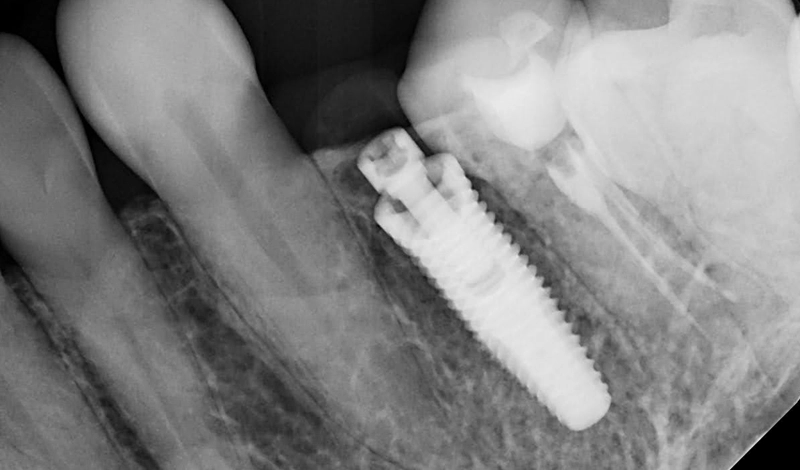

- Radiographs confirm that both implants (upper premolar and previously restored lower molar) are stable and well-integrated.

X-ray scans showing both implants placed in the upper premolar and lower molar positions